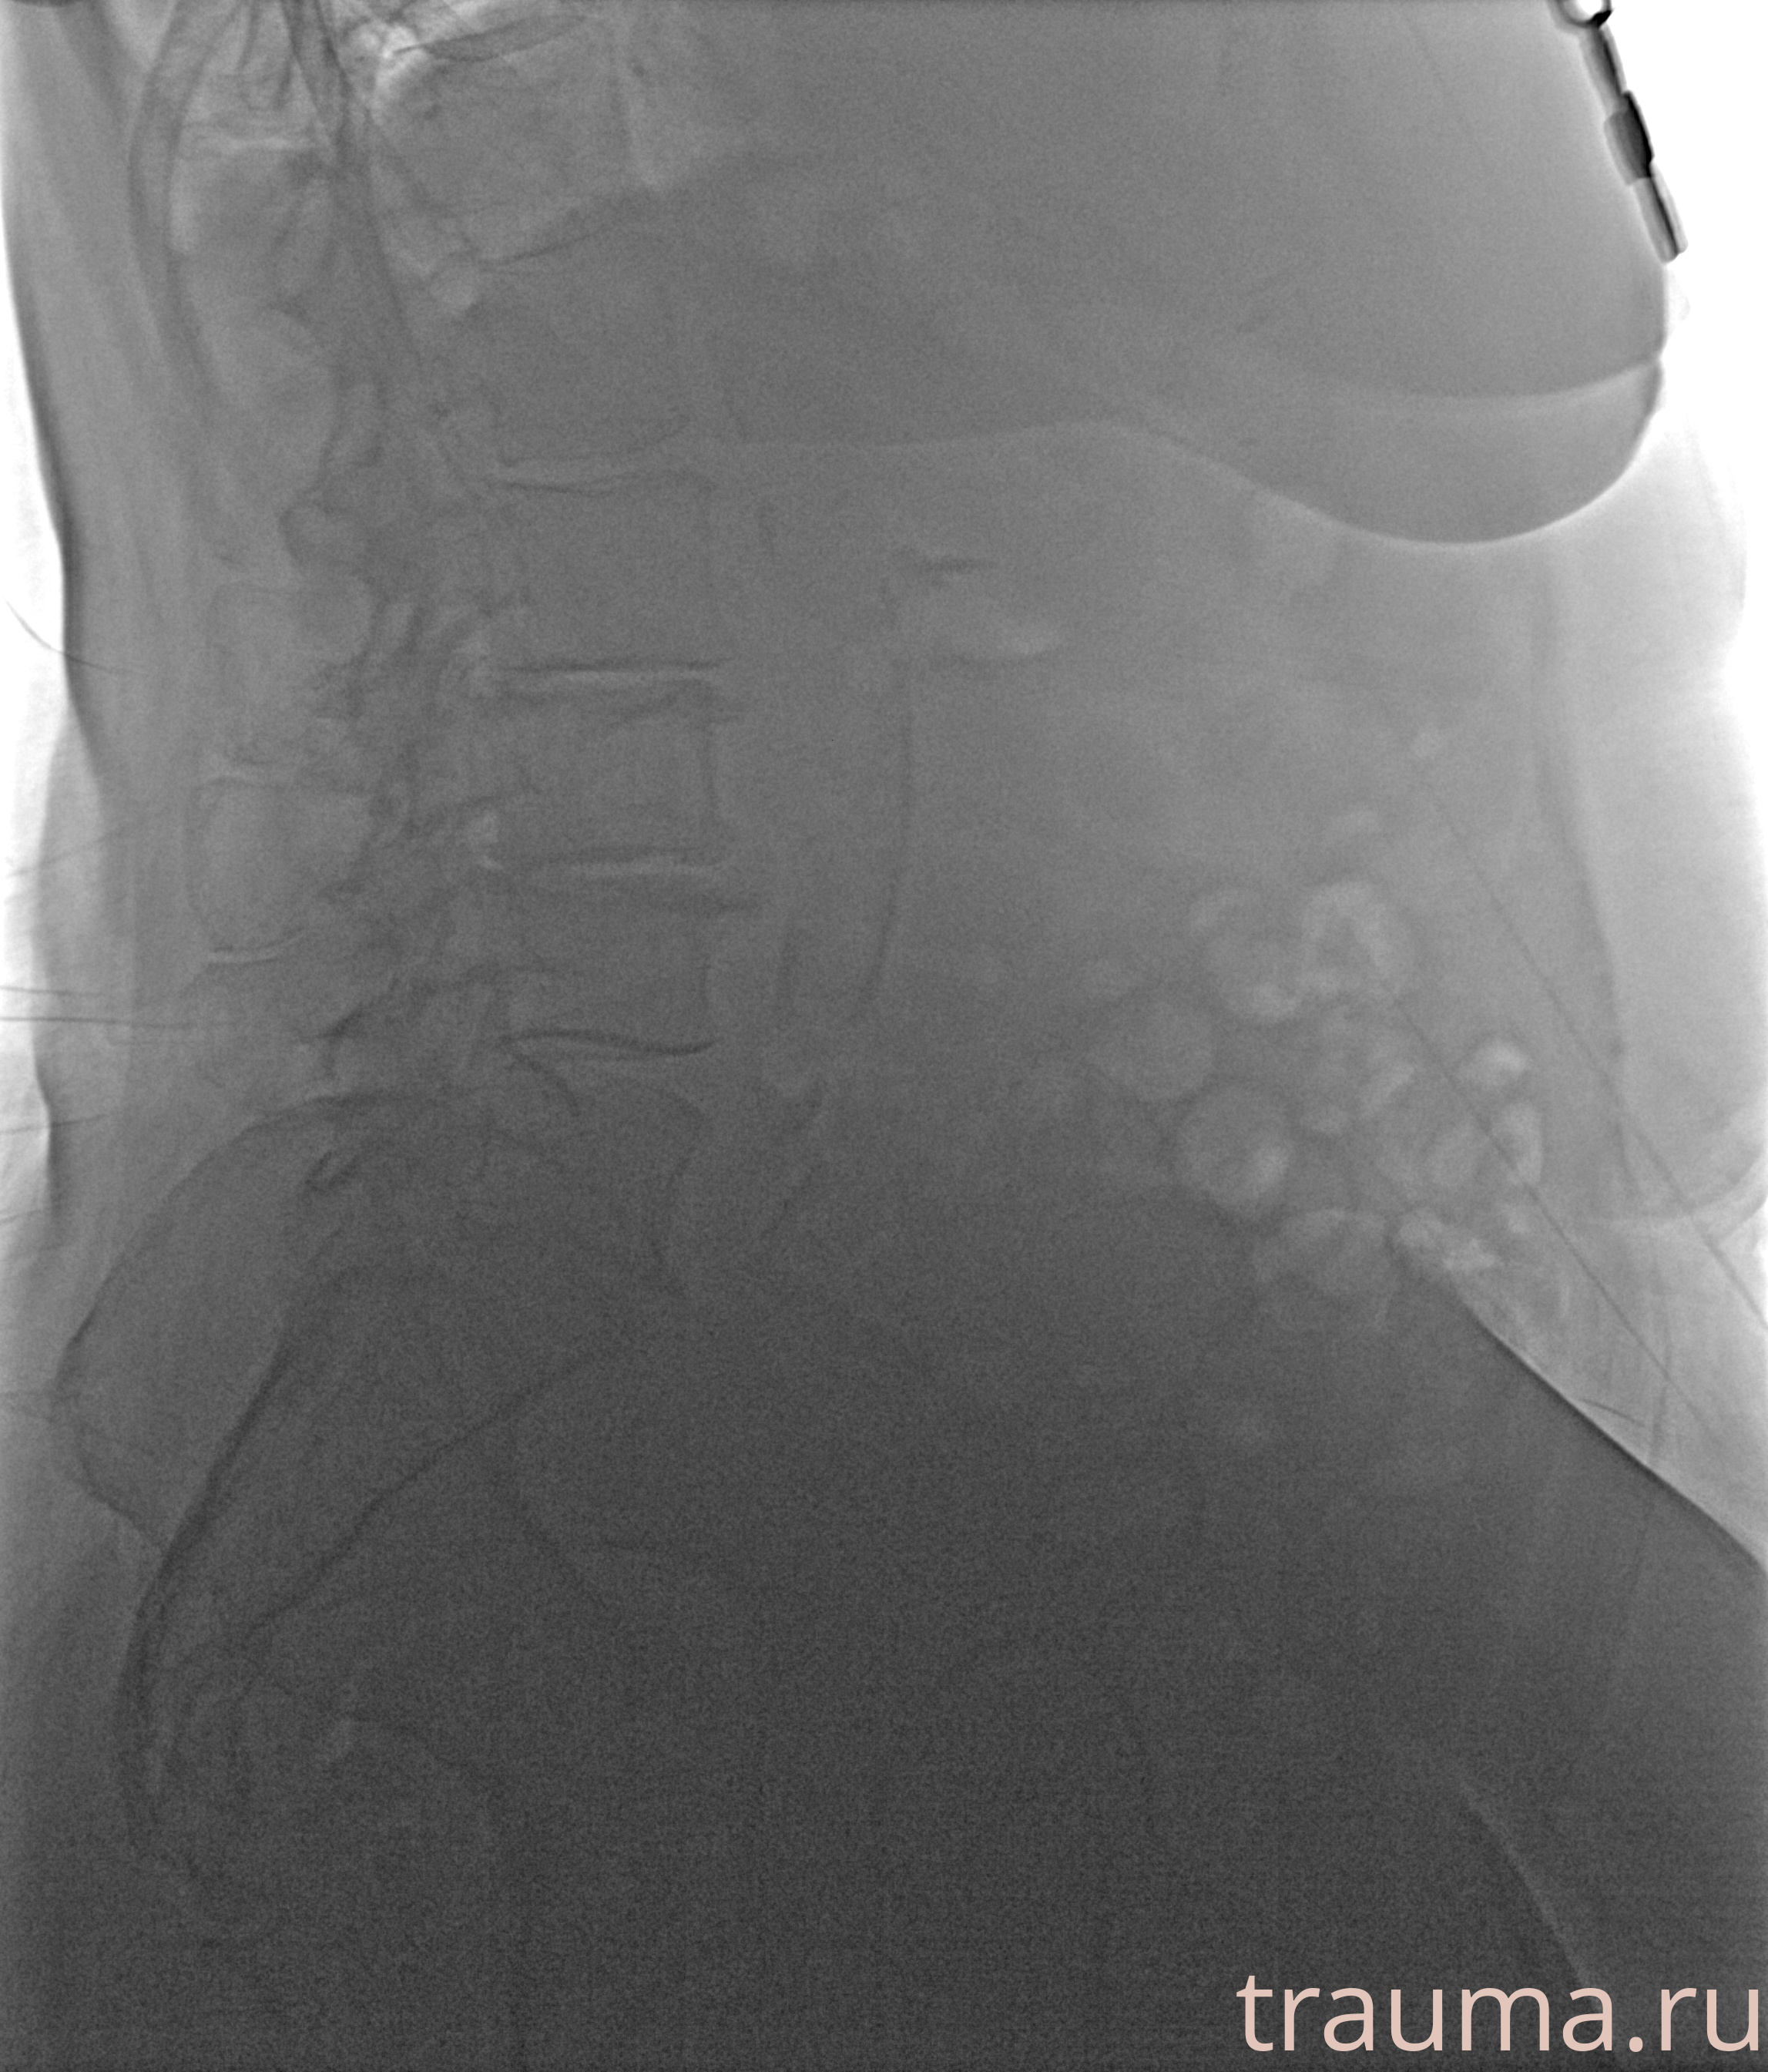

Рентгенограммы

Левая

Рентген на дому: по вашему адресу приезжает врач-рентгенолог, травматолог-ортопед с мобильным рентгеновским аппаратом, проводит диагностику травмы или заболевания, делает необходимые рентгенограммы, дает рекомендации по дальнейшему лечению. Получить качественные снимки в домашних условиях возможно благодаря уникальной методике, разработанной МосРентген Центром для института  Склифосовского